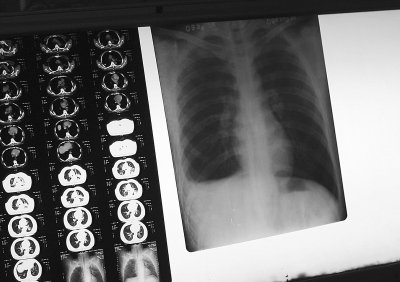

结核病“隐形”大国  与其他声势浩大的瘟疫不同,这场名叫结核病的瘟疫仿佛是“隐形”的。  大多数人觉得它已经远去了。作为常年致力于结核病防治的专家,钱秉中常常会遇到人们疑惑的询问:“肺结核,那不是旧社会的...

辽宁省肺结核患病率为130.8/10万,10万人中,将近131个感染。  3月24日是第16个“世界防治结核病日”,今年的宣传主题是“遏制结核 共享健康”。  昨日,辽宁省卫生厅、辽宁省疾病预防控制中心、辽宁省防痨协会联合...